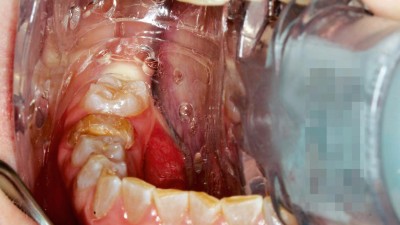

Sofortimplantation bei einer parodontal kompromittierten Patientin nach abgeschlossener kieferorthopädischer Behandlung im Erwachsenenalter

Die implantologische Versorgung parodontal kompromittierter Patienten erfordert ein hohes Maß an interdisziplinärer Planung und klinischer Präzision. Im vorliegenden Fallbericht wird die Versorgung einer Patientin mit fortgeschrittener Parodontalerkrankung beschrieben, bei der im Anschluss an eine abgeschlossene kieferorthopädische Therapie ein nicht erhaltungswürdiger Frontzahn extrahiert und unmittelbar durch ein Implantat ersetzt wurde. Dabei stellten sich mehrere Herausforderungen...